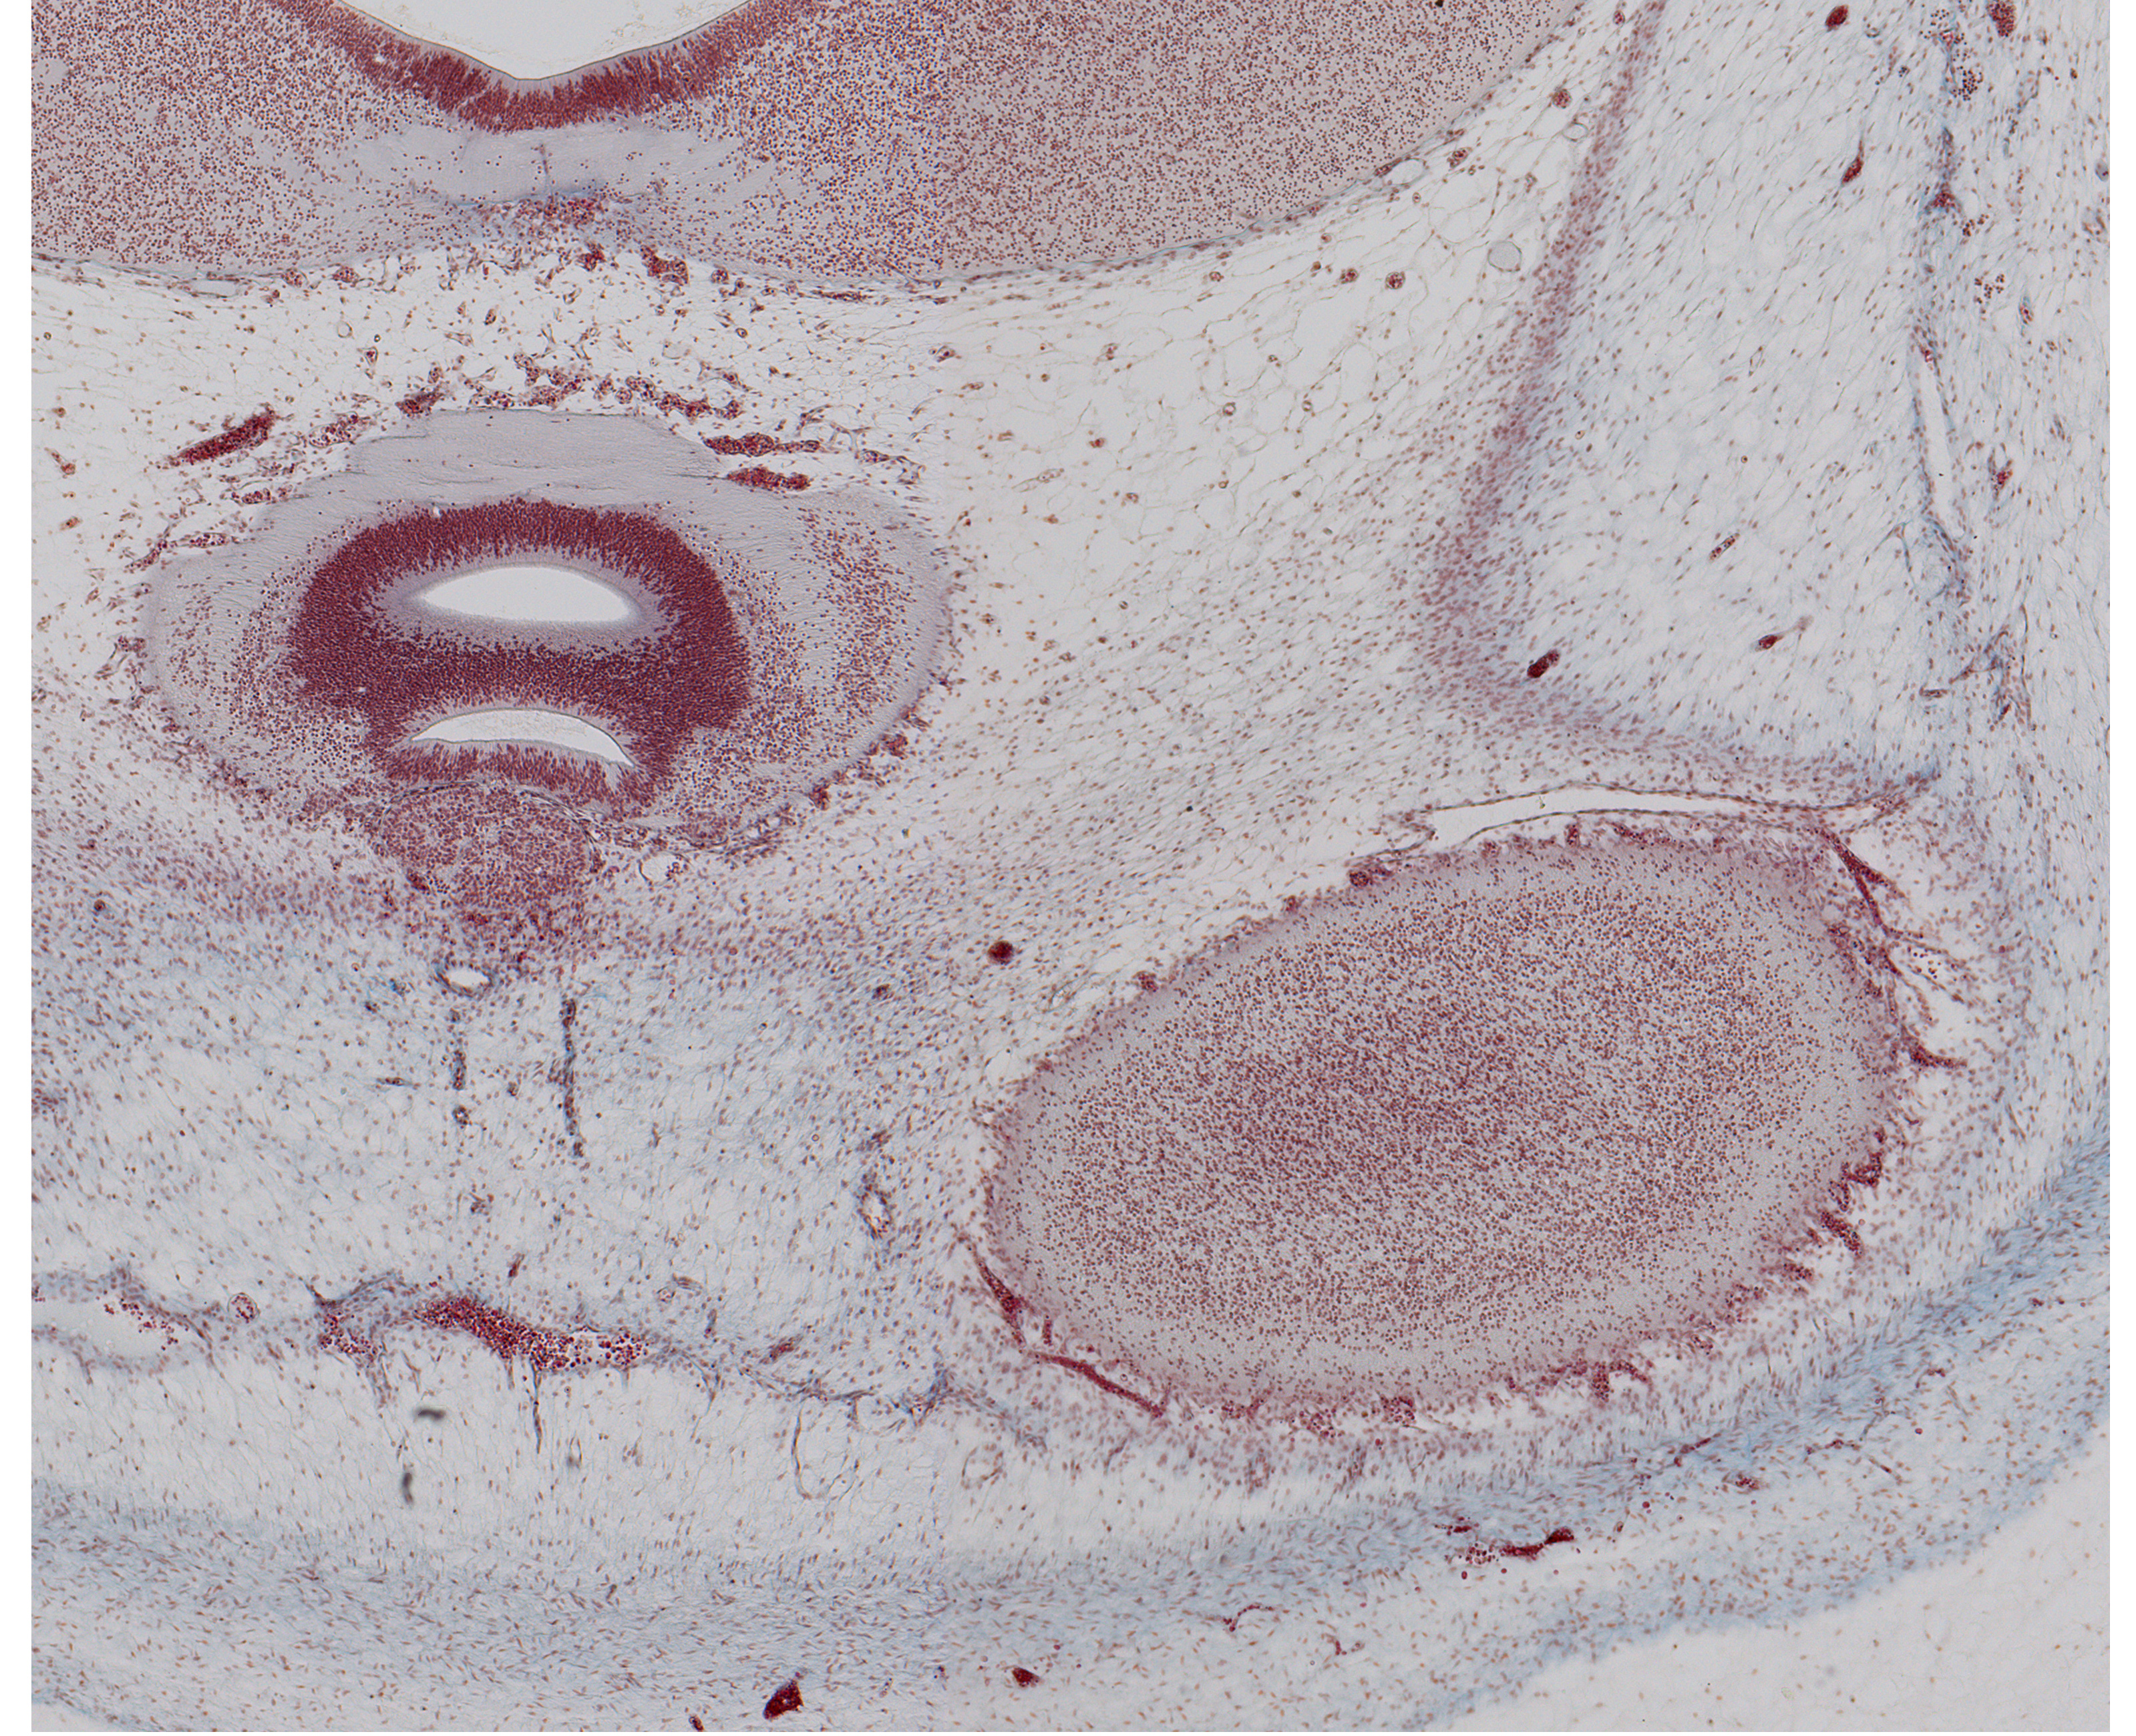

Tissue

–

Epiphysis, Pineal Recess, and Edge of Cerebral Hemisphere

Carnegie Embryo #9226

Location:

14-01-01